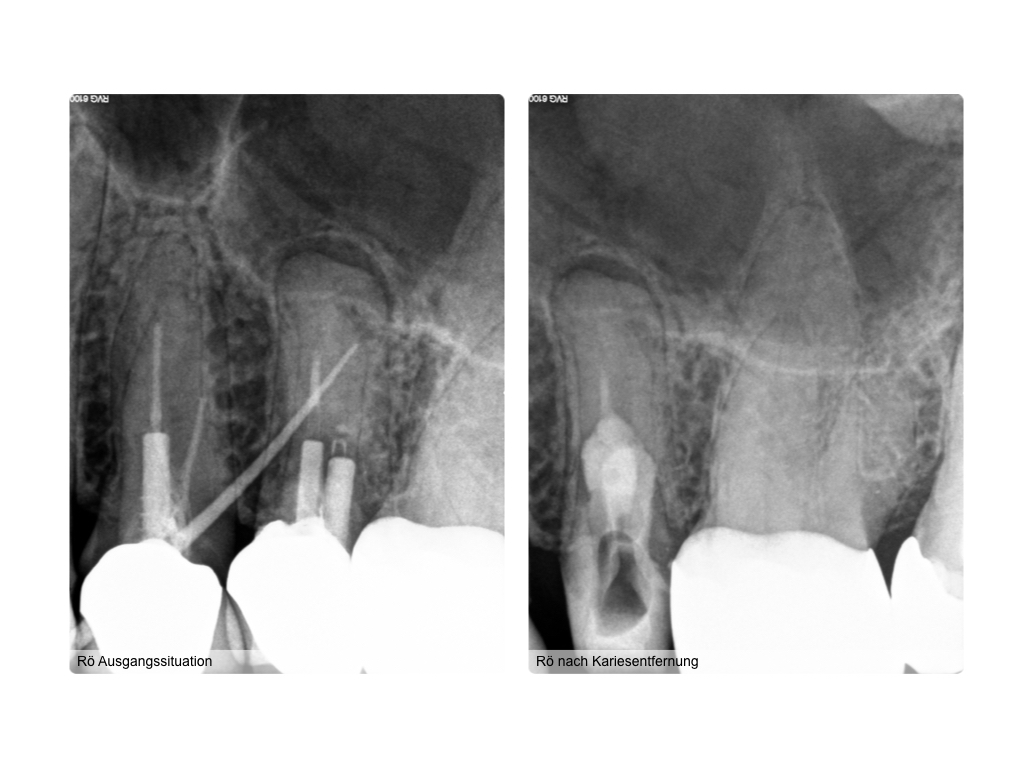

WS_Fallvorstellung23_06_8352.001 Veröffentlicht 23. Juni 2016 am 1024 × 768 in Wurzelkaries intrakanalär